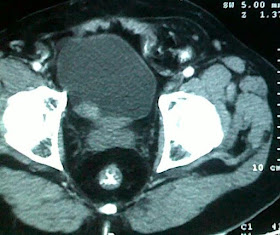

CASE: Choledochal cyst type 1^-www.drkeyurbhatt.in*

12 yrs girl with h/o cholangitis 15 days back

worked up and detected to have type one choledochal cyst.

CECT:

SURGERY: CDC excision and HJ

Pt discharged on POD 6.